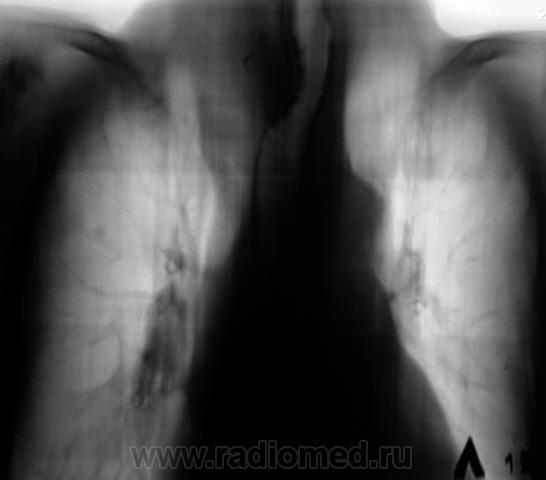

Экспансивно растущее об"емное образование верхнего средостения, неоднородной структуры за счет включений кальция. Состоит ли на учете у эндокринолога? Похоже на "ныряющий" зоб.

На учете не состоит. О патологическом процессе ранее было ничего не известно. "Выцепили" сегодня, сегодня и дообследовали.